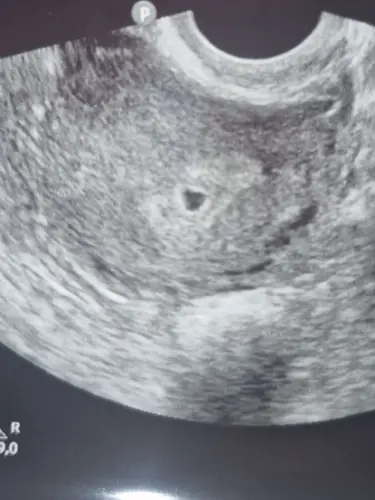

Wat zei de echoscopist?

Die zei aleen dat het op de goede plek zat

Moet z eh hen dat mijn burchtzakje bij 5 weken wat groter was, maarrrr niet getreurd want ik denk dat dat niets hoeft te zeggen! Ze zagen ook geen hartslag of iets dergelijks toen en twijfelde of het goed was, maar lig toch hier met een 2 maanden oude baby op mijn borst!

Denk dat als het echt niet goed zat ze dat had gezegd! 馃挒